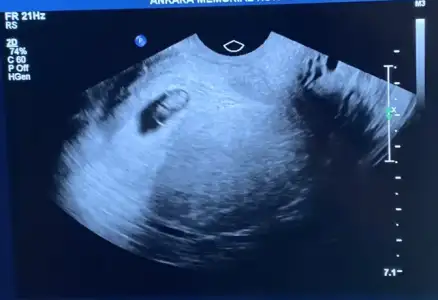

H hayaletcizgi canım merhaba benim için de tahmin yapabilir misin, 7+4 vajinal ultrason. plasenta neresi çözemedim ben 🥰

• 8BE8B3A5-CCB0-492E-A086-3EF1EF21F137.webp

8BE8B3A5-CCB0-492E-A086-3EF1EF21F137.webp

14,4 KB · Görüntüleme: 50